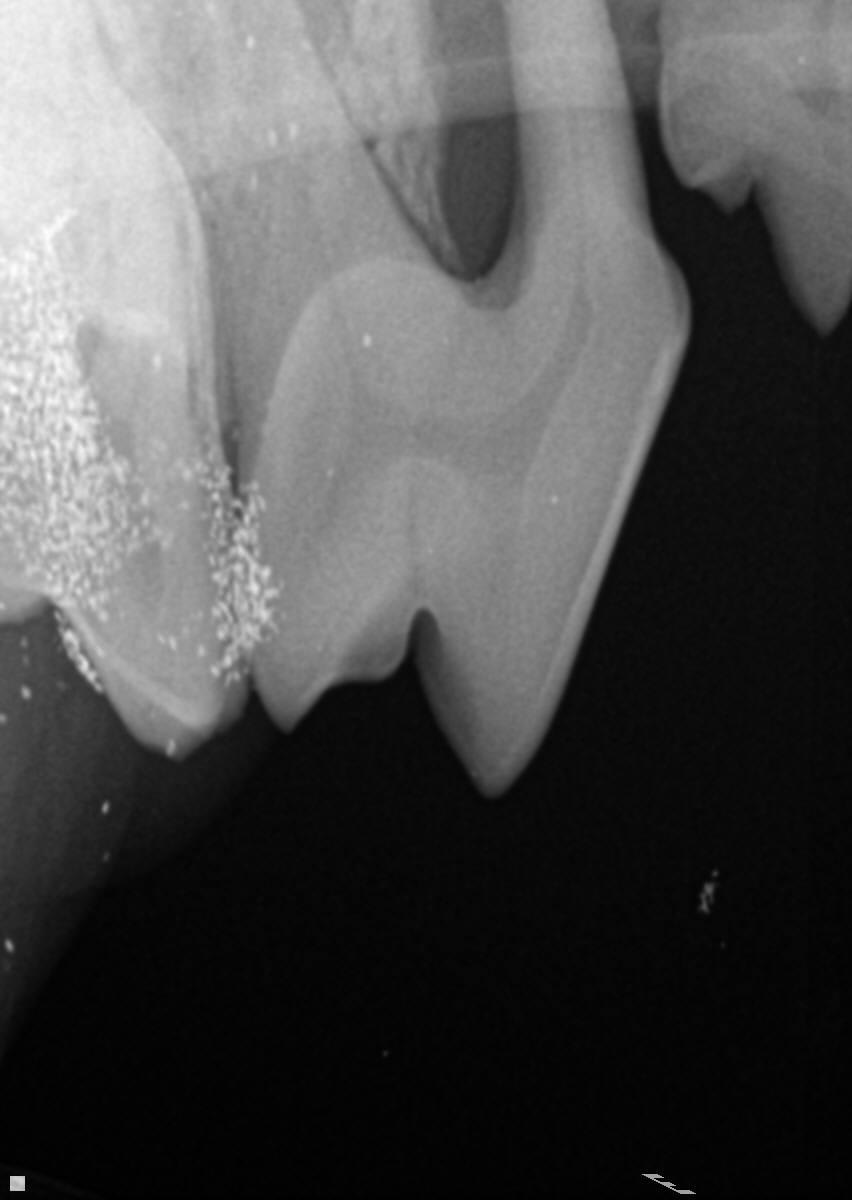

Our dog had his teeth cleaned a few months ago. During the cleaning the vet had concerns about his carnassial teeth. He said 1 root was exposed, 1 root was good, and 1 root was so-so. He said it was somewhat rare and initially said we could "wait and see" or go to an expert. However, he later changed his mind and said they should be removed. I wondering if they really need to come out. My dog does not appear to be in any pain.

Based on the attached pictures, I would recommend removal of the carnassial tooth as well as the too the next to it. There is significant loss of bone around the roots and should really come out now. The vet may have recommended referral to a vet with more experience as these teeth can be challenging to remove due to their size, location, and number of roots.